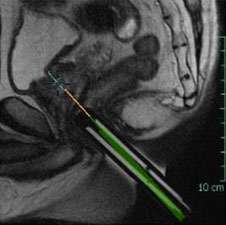

LEFT: Oblique Axial T2-weighted image from in-bore MR-guided targeting

RIGHT: Corresponding sagittal T2-weighted image from in-bore MR-guided targeting

- Gleason grade 3+3=6/10

- All biopsies over 5 mm and over 50% of core